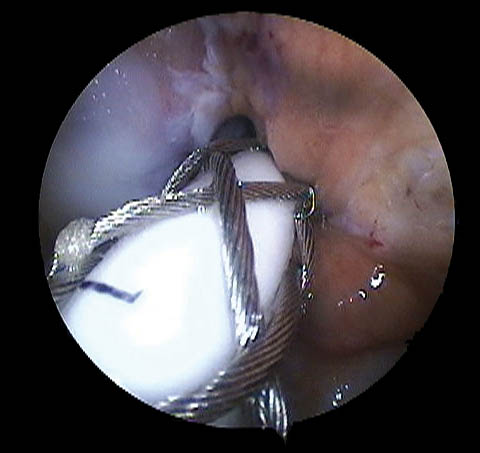

Respecto a su morfología usamos la clasificación de Lage et al.28 (Figs. 9, 10 y 11) que se distribuyeron de la siguiente manera:

-

58.6% Colgajo radial.

26.1% Fibrilada.

14.2% Longitudinal periférica.

1.1% Inestables.

Figura 11.